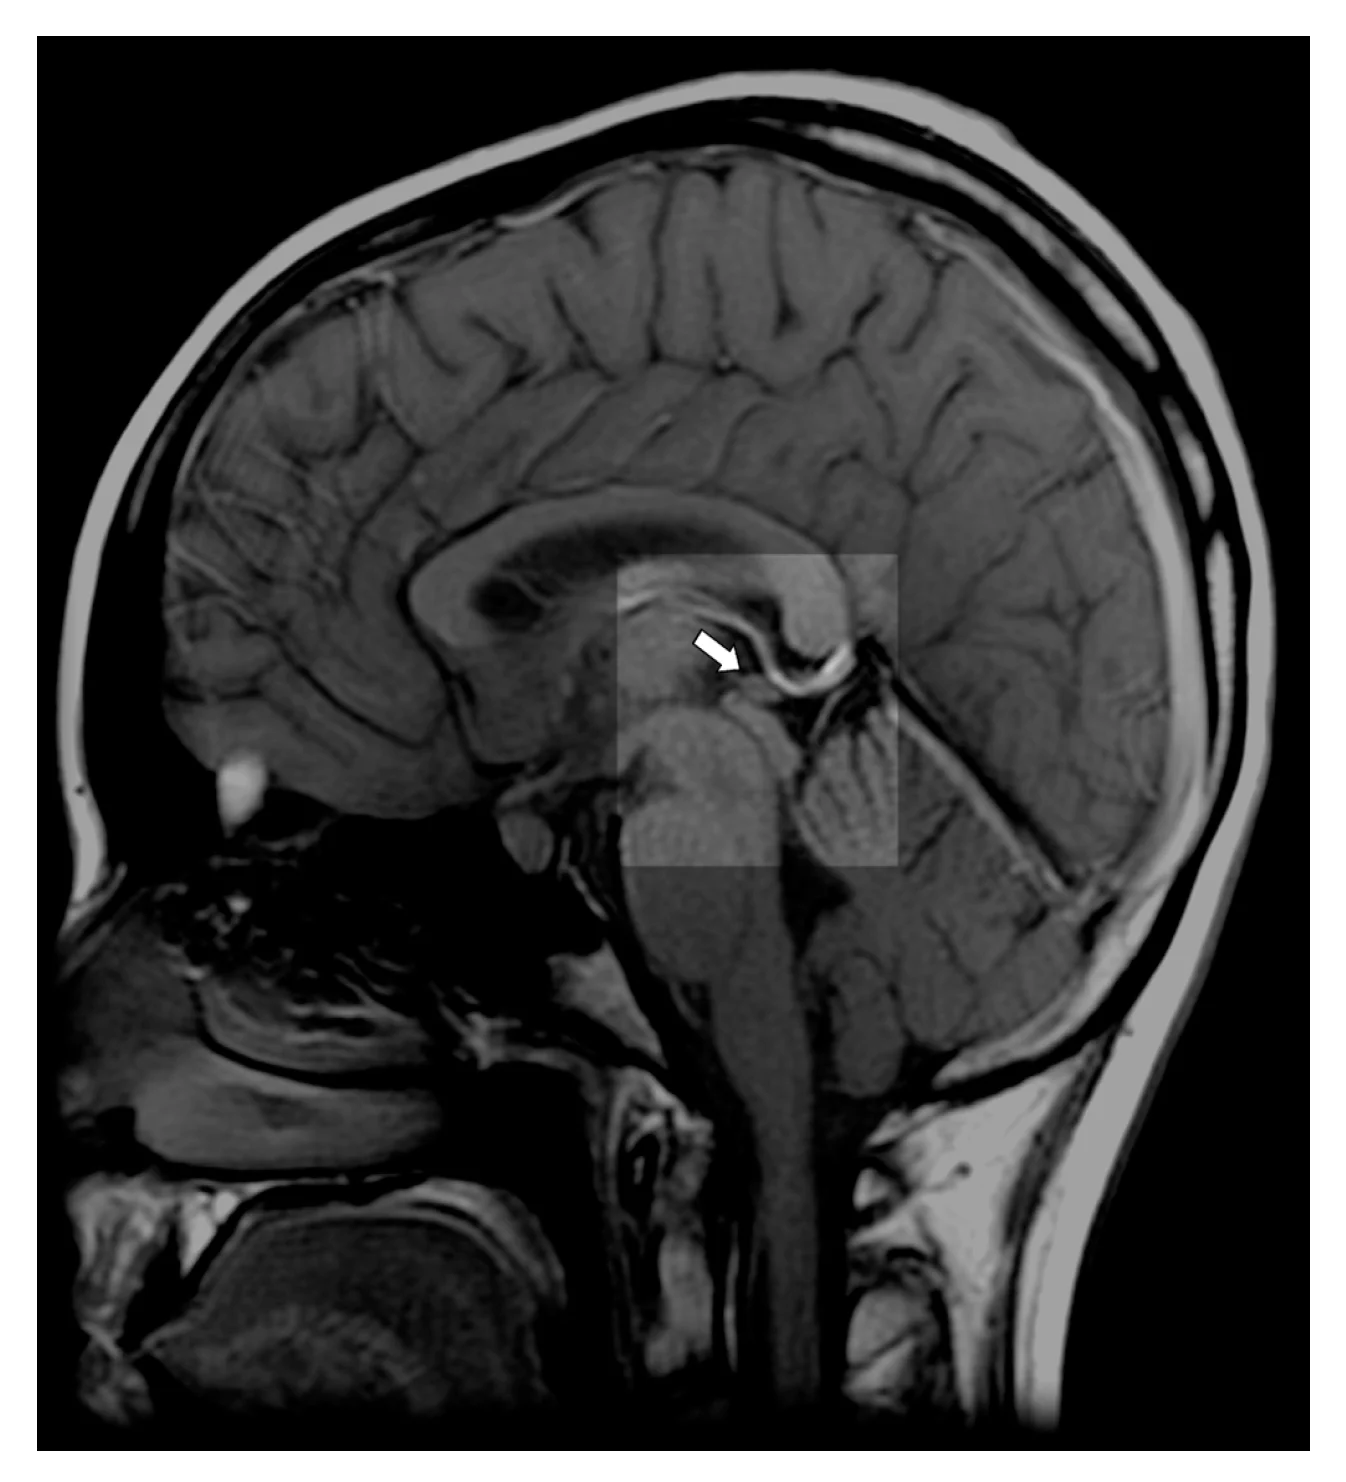

Kalbama apie kankorėžinę liauką – vos kelių milimetrų dydžio darinį, esantį smegenų viduryje. Nors šiandien ji siejama su hormonų gamyba ir miego reguliavimu, XVII amžiuje jai buvo suteikta kur kas didesnė reikšmė. Prancūzų filosofas Renė Dekartas ją laikė savotišku tiltu tarp kūno ir proto.

Dekartas manė, kad ši liauka sujungia signalus iš akių, ausų ir kitų jutimo organų į vieną patirtį, kuri vėliau „pateikiama“ sielai. Tačiau šiuolaikinė neurologija šią idėją paneigė. Mokslininkai šiandien aiškiai žino, kad kankorėžinė liauka atlieka visai kitą, nors ir labai svarbią funkciją – ji gamina melatoniną ir reguliuoja žmogaus cirkadinį ritmą, kitaip tariant, biologinį laikrodį.

Šiandien mokslas pripažįsta tik tiek, kad kankorėžinė liauka iš tiesų gali kalkėti su amžiumi. Tačiau kodėl tai vyksta, vis dar nėra iki galo aišku. Viena žinoma tikrai – šis procesas neturi nieko bendra su dvasiomis, energijomis ar sąmonės „užblokavimu“.